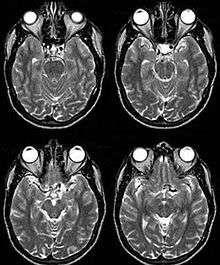

Fig. 2

Internal Carotid Artery dolichoectasia is particularly interesting because the artery normally already contains one hairpin turn. Seen in an MRI as two individual arteries at this hairpin, a carotid artery dolichoectasia can progress so far as to produce a second hairpin turn and appear as three individual arteries on an MRI. In the case of a dolichoectasia of the Internal Carotid Artery (ICD), the pathogenesis is primarily related to compression of the Optic Nerves at the Optic Chiasma (see Fig. 1 and 2).